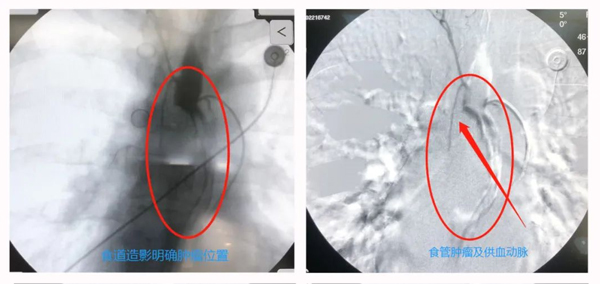

从以下图片可以看到口服食道造影后,明确肿瘤的位置,经过导管造影找到这个位置的肿瘤供血血管,精准插管向肿瘤供血区域注射少量化疗药物,栓塞肿瘤供血动脉。达到高效化疗、最低副作用的目的。两名患者均无任何不适感受。